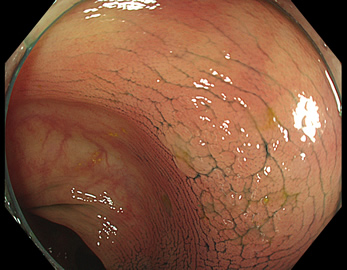

特に、下のような「Ub型(全く凸凹の無い完全に平坦な病変)」は、以前は「ほとんど見つからなかった」のが、TXIを使うようになってから「日常的に」見つかるようになりました。

通常観察 TXIモード

青い色素は追加していません![]()